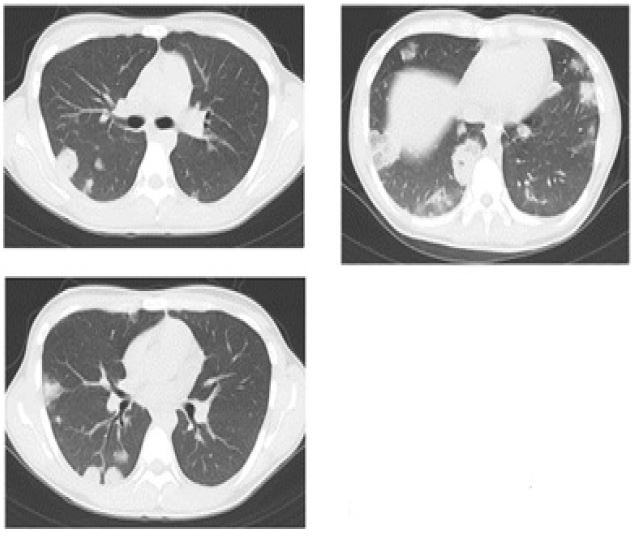

The results of the blood tests and Computed Tomography (CT) scans are displayed in Table 3. The levels of inflammatory markers displayed a significant increase, whereas the markers of renal function and coagulation were also severely impaired. Plain CT scan revealed multiple bilateral shadows in the lungs (Figure 1). We assessed multiple organ failure as a result of sepsis caused by soft tissue infection or pneumonia of the COVID-19. However, contrast-enhanced CT revealed a low-density intraluminal thrombus in the left jugular vein (Figure 2). We diagnosed LS and assessed lung shadows and soft tissue swelling as secondary findings.

Figure 1: The plain CT scan revealed multiple shadows in the bilateral lung.